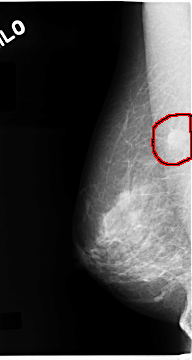

C_0115_1.RIGHT_MLO

RIGHT_MLO LINES 4680 PIXELS_PER_LINE 2496 BITS_PER_PIXEL 12 RESOLUTION 50 OVERLAY

FILE: C_0115_1.RIGHT_MLO.OVERLAY

TOTAL_ABNORMALITIES 1

ABNORMALITY 1

LESION_TYPE MASS SHAPE ROUND MARGINS SPICULATED

ASSESSMENT 5

SUBTLETY 5

PATHOLOGY MALIGNANT

TOTAL_OUTLINES 1

BOUNDARY